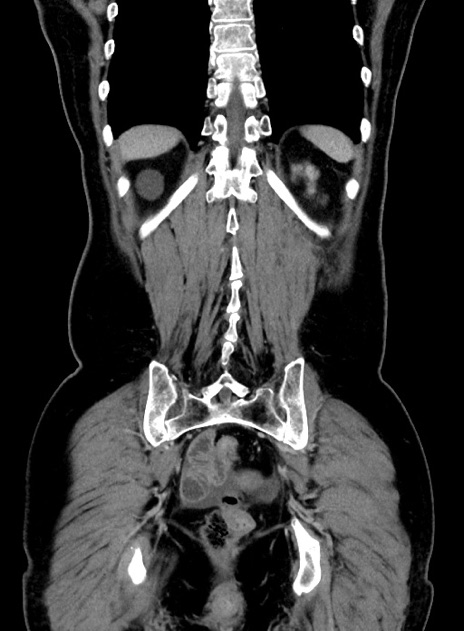

症例9(冠状断像)

【症例】 60歳代女性

【主訴】むかつき、みぞおちの痛み

【現病歴】3日前よりむかつきがあり、食事がとれない。

【既往歴】糖尿病

【身体所見】発熱なし、心窩部圧痛軽度あるも、腹膜刺激症状なし。

【データ】WBC 7400、CRP 1.92